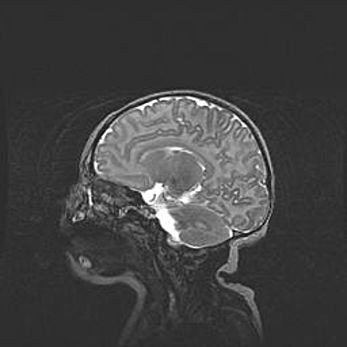

Церебральная ишемия II.

Возраст: 7 дней

Вес: 3350 г

Пол: женский

Окружность головы: 35 см

Срок гестации: 39 недель

Ишемия головного мозга – это состояние, которое развивается в ответ на кислородное голодание вследствие недостаточного мозгового кровообращения. У новорожденных она является следствием дефицита кислорода, что ведет к метаболическим расстройствам различной степени тяжести в тканях головного мозга, в том числе к развитию коагуляционных некрозов и гибели нейронов.